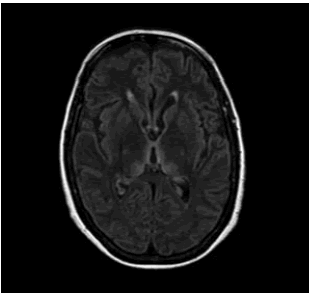

¿Qué es la mielopatía por infección del virus de la leucemia de células T humanas?

El virus de la leucemia de células T humanas tipo 1 (HTLV-1) es un retrovirus humano que pertenece a la familia Retroviridae, subfamilia Orthoretrovirinae, y al género Deltaretrovirus. Este agente…